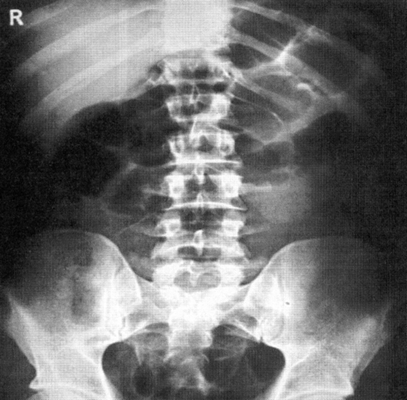

Рентгенография брюшной полости

Рентген активно используется для диагностики заболеваний органов брюшной полости. Широко распространена обзорная рентгенография брюшной полости – рентгенографическое исследование без введения контрастного вещества, позволяющая получить общую картину состояния брюшной полости.

Что показывает рентген брюшной полости?

Метод рентгендиагностики основан на том, что ткани различной плотности по-разному поглощают рентгеновские лучи. Более плотная, например, костная ткань хуже пропускает лучи, поэтому на снимке такая ткань оказывается светлее. Метод позволяет определить местоположение органов, их целостность, наличие инородных тел и новообразований.

Рентгенография брюшной полости показывает:

- как распределены газ и жидкость в брюшной полости, присутствует ли в брюшной полости свободная жидкость;

- присутствуют ли в брюшной полости инородные тела (проглоченные предметы в кишечнике, камни в желчном пузыре, камни в почках);

- имеются ли повреждения внутренних органов;

- имеет ли место внутрибрюшное кровотечение.

Рентген брюшной полости

С точки зрения оценки состояния конкретных органов обзорная рентгенография брюшной полости не очень информативна, однако она позволяет быстро определить, является ли картина патологической или нет. При разрыве стенки желудка или кишечника (прободение язвы или разрушении стенки опухолью) рентген покажет выходящий в свободную брюшную полость газ. С помощью рентгена брюшной полости можно диагностировать непроходимость кишечника и даже определить примерное место локализации проблемы.